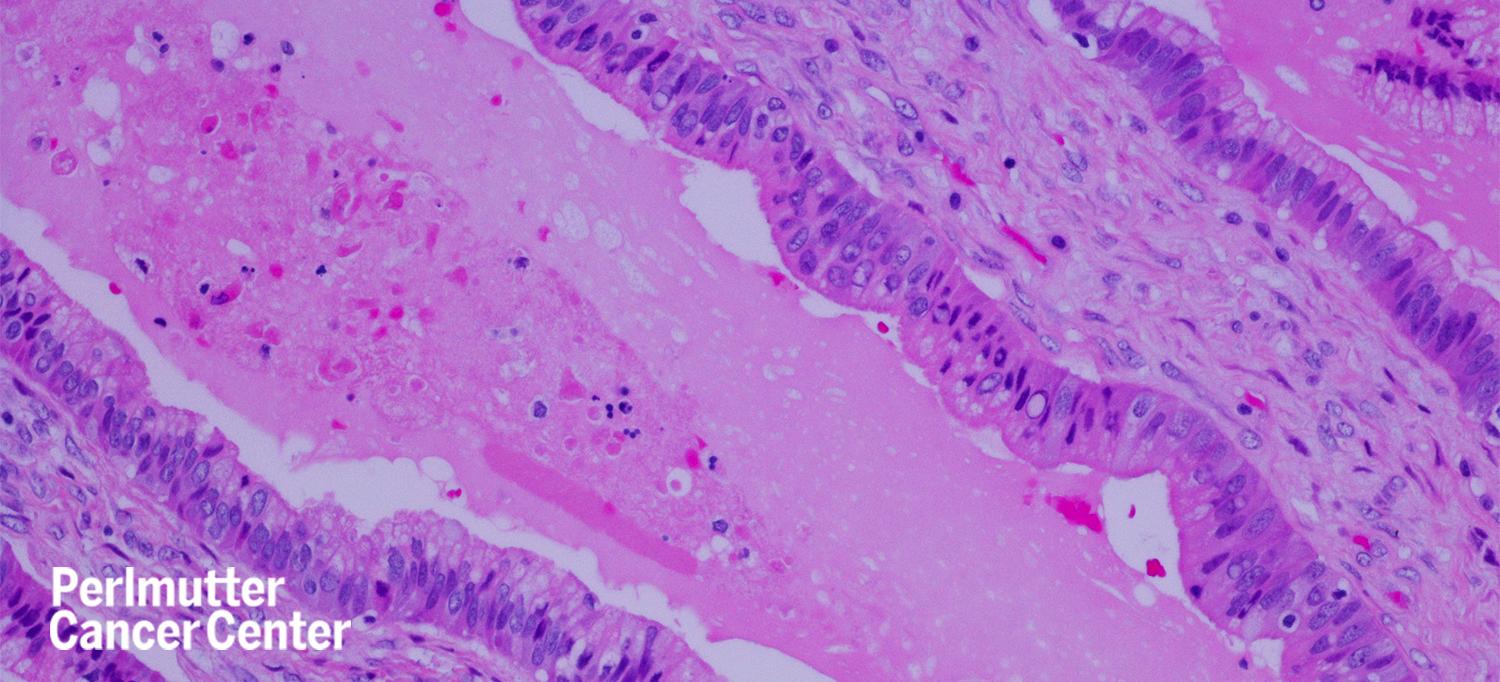

An experimental treatment for metastatic pancreatic cancer with the KRAS-G12D gene mutation shrank tumors in a person with the disease by 72 percent after 6 months of treatment, according to a report in The New England Journal of Medicine.